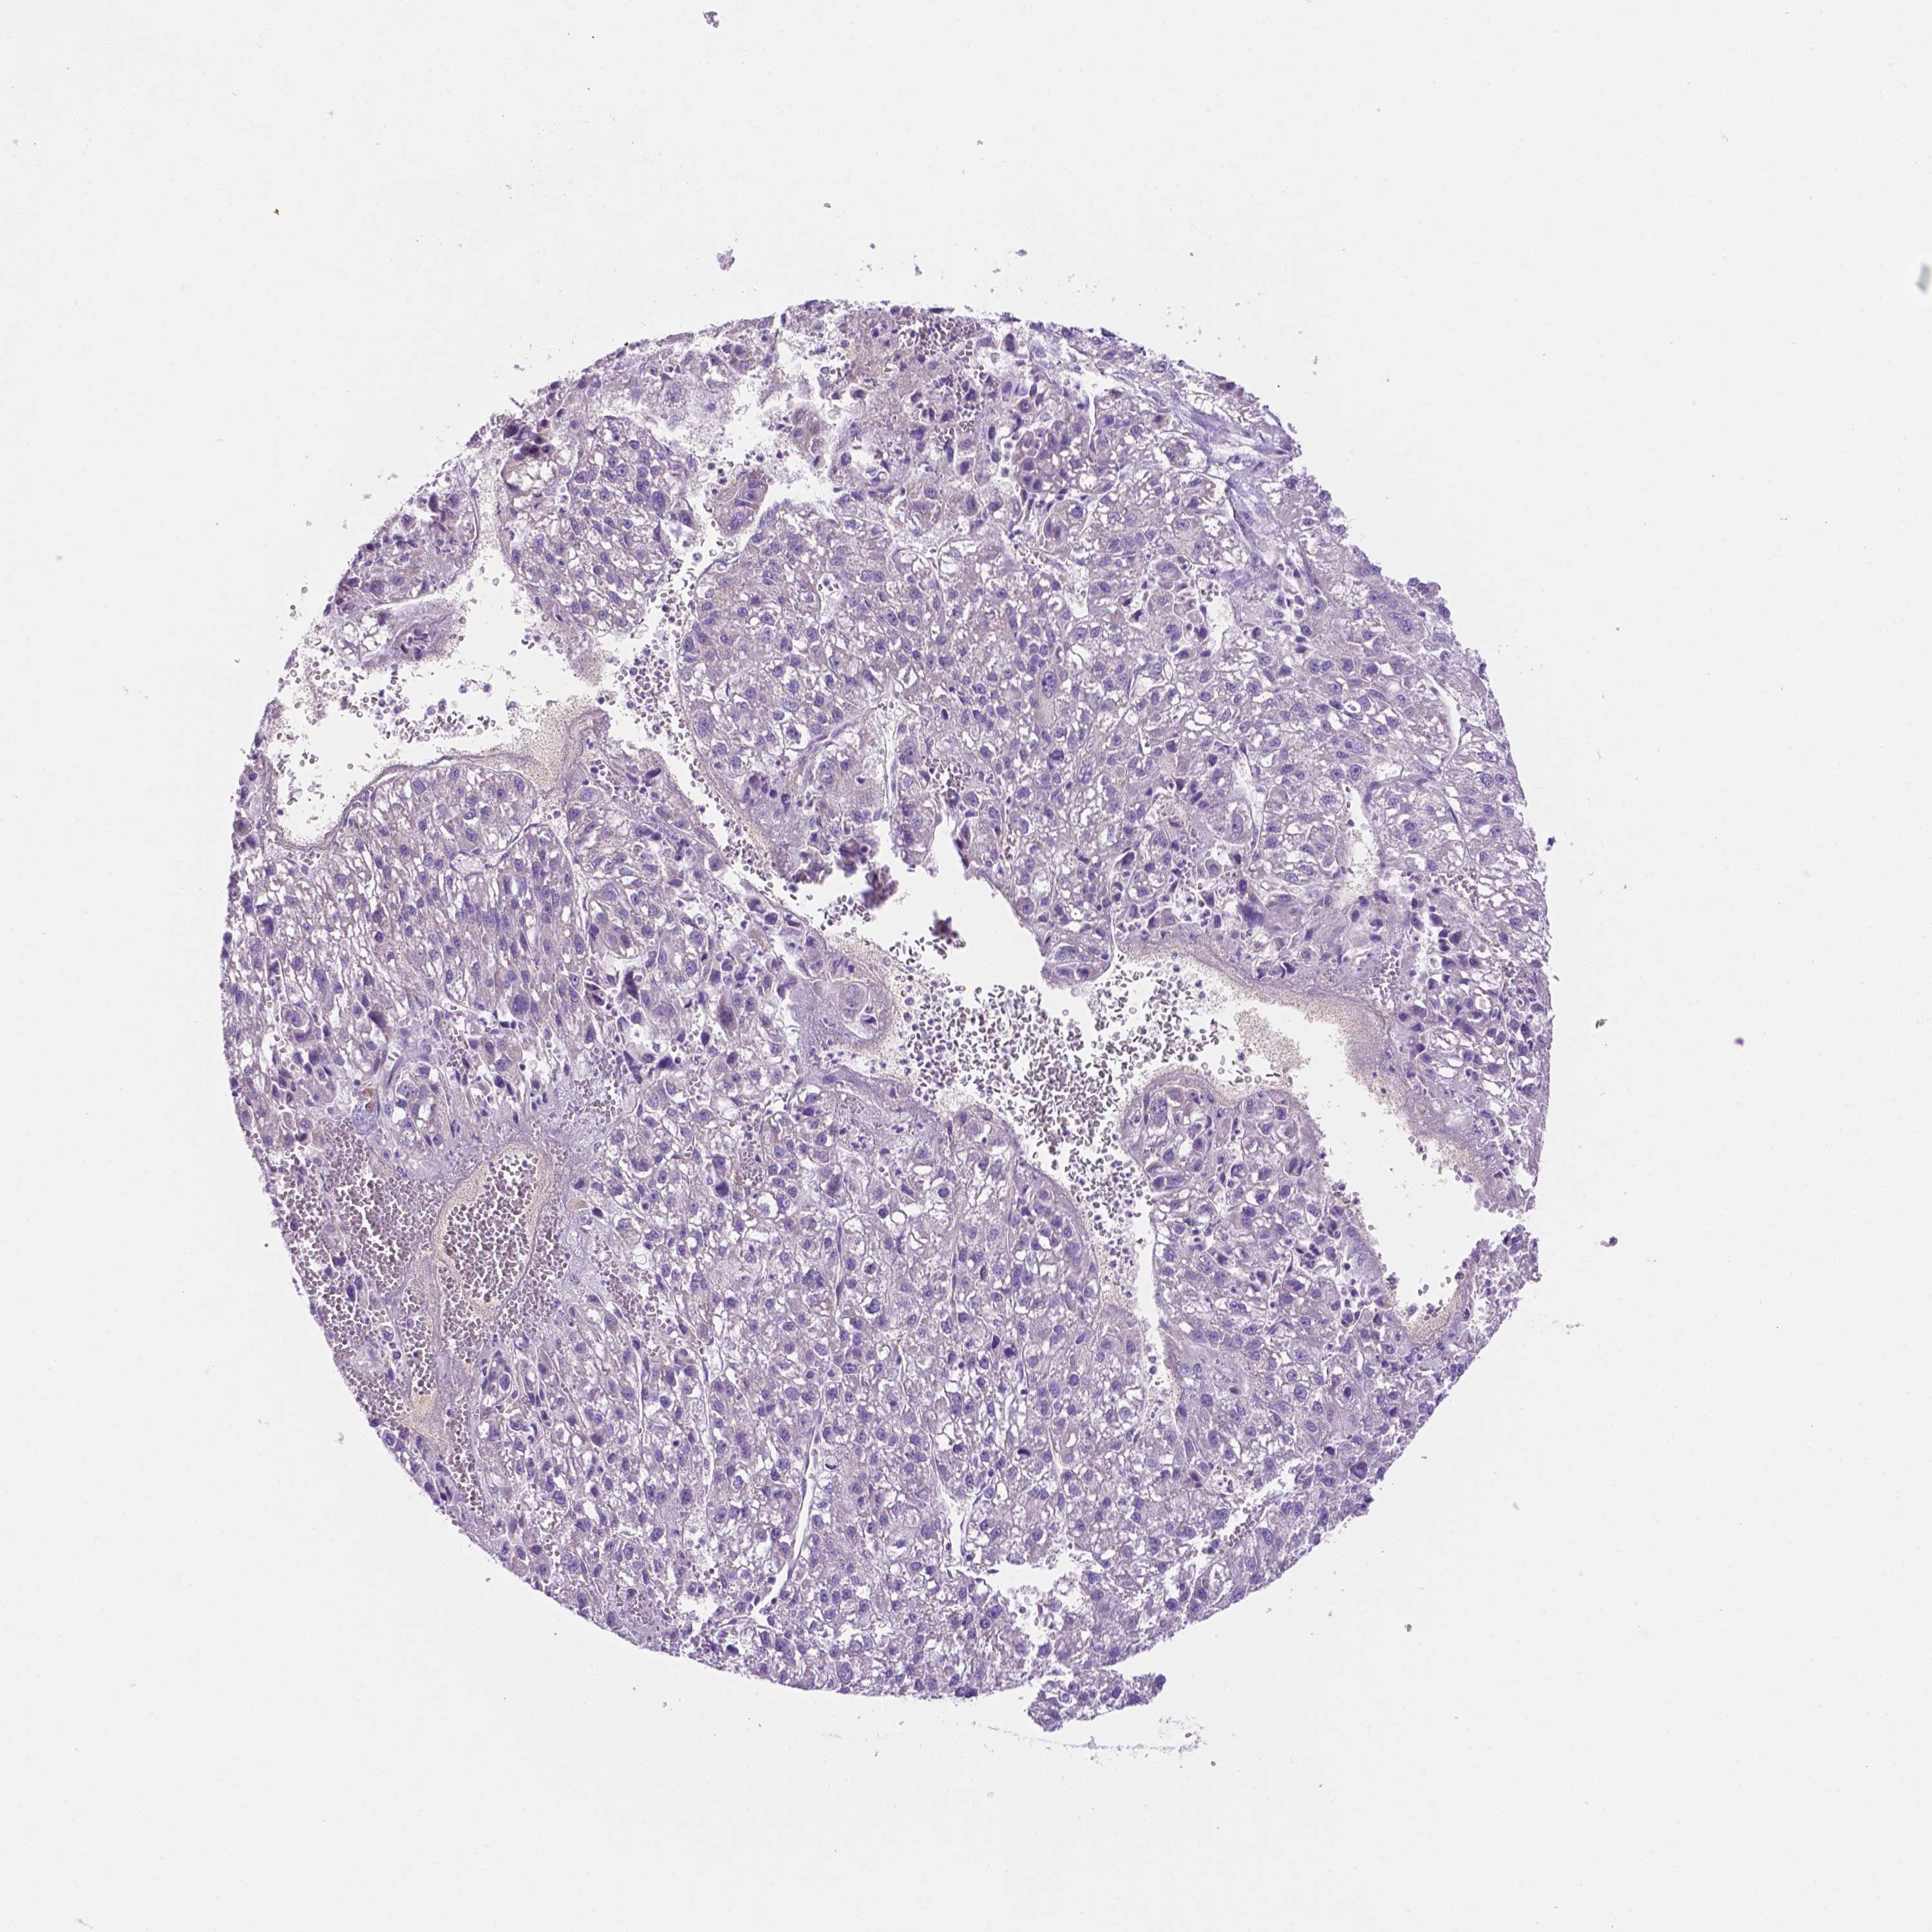

CEACAM7